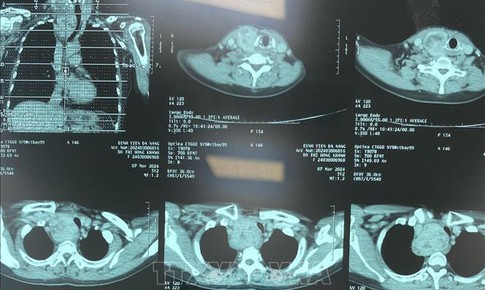

Ứng dụng AI trong chẩn đoán hình ảnh, siêu âm... giúp bác sĩ giảm tải, người bệnh giảm chờ đợi kết quả

Y tế - 24/08/2024 10:37SKĐS - Theo dự báo của Tổ chức Y tế thế giới đến năm 2030, toàn cầu sẽ thiếu khoảng 18 triệu nhân viên y tế. Vì thế việc ứng dụng trí tuệ nhân tạo (AI) trong chẩn đoán hình ảnh không chỉ cho kết quả chính xác cùng các phân tích dữ liệu nhanh nhạy mà còn giúp bác sĩ giảm tải...

PGS.TS Lương Ngọc Khuê: Đưa AI chẩn đoán hình ảnh giúp phát hiện ung thư giai đoạn sớm

Y tế - 13/01/2024 18:44SKĐS - PGS.TS Lương Ngọc Khuê cho hay, việc đưa AI trong hệ thống chẩn đoán hình ảnh giúp các bác sĩ tầm soát phát hiện các bệnh ung thư phổ biến ở giai đoạn sớm ở Việt Nam.

Việt Nam ứng dụng, làm chủ nhiều kỹ thuật cao trong chẩn đoán hình ảnh

Y tế - 12/01/2024 16:48SKĐS - Những năm gần đây, y học Việt Nam có nhiều tiến bộ, đặc biệt là chuyên ngành chẩn đoán hình ảnh đã đẩy mạnh ứng dụng trí tuệ nhân tạo (AI) trong sàng lọc, phát hiện sớm và chẩn đoán một số bệnh như ung thư, tim mạch, tiêu hoá, xương khớp…